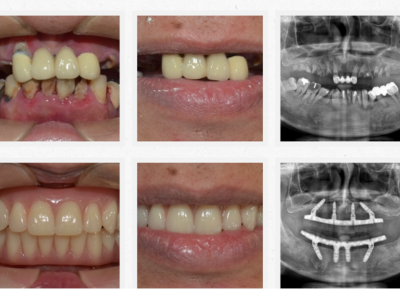

專業醫師,守護你的笑容 我們結合國際級植牙系統與數位美學技術,提供無痛、精準、快速的牙科治療體驗。從植牙、全瓷冠到隱形矯正,一次滿足你的需求。 預約諮詢 關於我們 精準重建每一個笑容 陳俊岳醫師率領的專業團隊,結合國際植牙技術與數位牙科系統,專精於微創植牙、全口重建、全瓷冠與隱形矯正。我們相信醫療不只是技術的展現,更是傾聽與信任的累積,讓每位患者都能安心重拾自然笑容。 醫師介紹 你所需要的牙科服務,一次到位 從植牙、全瓷美學到隱形矯正,為你提供最適合的解決方案 All-on-4 全口重建 透過四支植體即可支撐全口固定假牙,手術當天即可恢復咀嚼與笑容。省時、安全,是全口重建的高效新選擇。 微創植牙 結合 3D 導引技術與數位影像分析,僅需微小切口即可完成植牙。傷口小、恢復快,是患者首選的無痛精準植牙方式。 全瓷貼片 / 全瓷冠 高透光全瓷材質,重現自然笑容。從牙齒美白、縫隙修飾到整體微笑設計,打造專屬自信風采。 隱形矯正 透明舒適、可自行摘戴,結合數位3D掃描與模擬,讓矯正過程幾乎隱形,同時維持生活自信與美觀。 服務項目 想擁有更自信的笑容我們幫你實現! 不論是植牙、貼片還是矯正, 專業醫師團隊都會為你量身打造最自然的治療方案。 一次預約,即可完成影像健檢與療程規劃。立即體驗數位牙科的高效與舒適。 預約諮詢 選擇我們 精準醫療 × 美學設計 × 人本關懷 專業與溫度兼具的牙科團隊 陳俊岳醫師帶領的團隊結合國際植牙系統、數位牙科技術與多年的臨床經驗,為每位患者量身打造最適合的治療方案。我們堅持以人為本,讓治療更安全、美觀且長久穩定。 精準定位、傷口小、恢復快 客製化笑容美學設計 傾聽需求、尊重選擇,讓醫療更有溫度 診療案例 患者見證 他們的笑容,證明一切 「以前害怕看牙,來這裡完全改觀。醫師很有耐心,手法也很細膩, 植牙後完全沒有不適,現在咬東西都很自然。」 陳小姐・植牙治療 「我做了全瓷貼片,笑起來真的差好多! 醫師幫我設計的牙齒形狀超自然,朋友都以為是我原本的牙齒。」 林小姐・全瓷貼片美學修復 「我選擇做 All-on-4 全口重建,手術當天就能吃東西, 整個過程比想像中輕鬆很多,非常感謝團隊專業又溫柔的照顧。」 黃先生・全口重建 立即撥打 02-25533202 台北市大同區承德路二段176號 (捷運民權西路站2分鐘) 官方Line預約諮詢 台北院所 預約專線 02-25533202 台北市大同區承德路二段176號 (捷運民權西路站2分鐘) 台南院所 預約專線 06-3117111 台南市永康區中華二路189號 官方Line預約諮詢